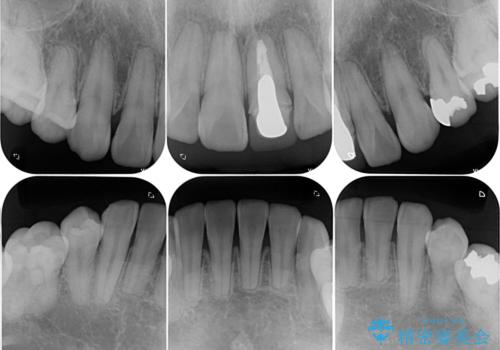

- 口元の突出感を改善するための抜歯矯正を終えた患者様ですが、幼少期からの変色した歯をセラミッククラウンにて自然な色合いに変えていくこととしました。

近年では大変珍しいですが、胎児あるいは乳幼児期の抗生物質の影響で永久歯が変色してしまうことがあります。

ホワイトニングでの改善は期待できないため、オールセラミッククラウンによる補綴治療が必要となります。